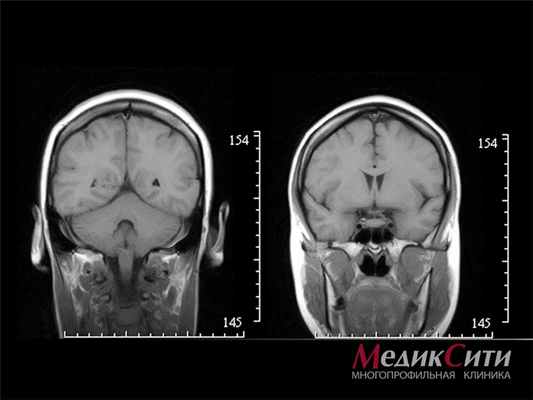

![]()

МРТ головного мозга